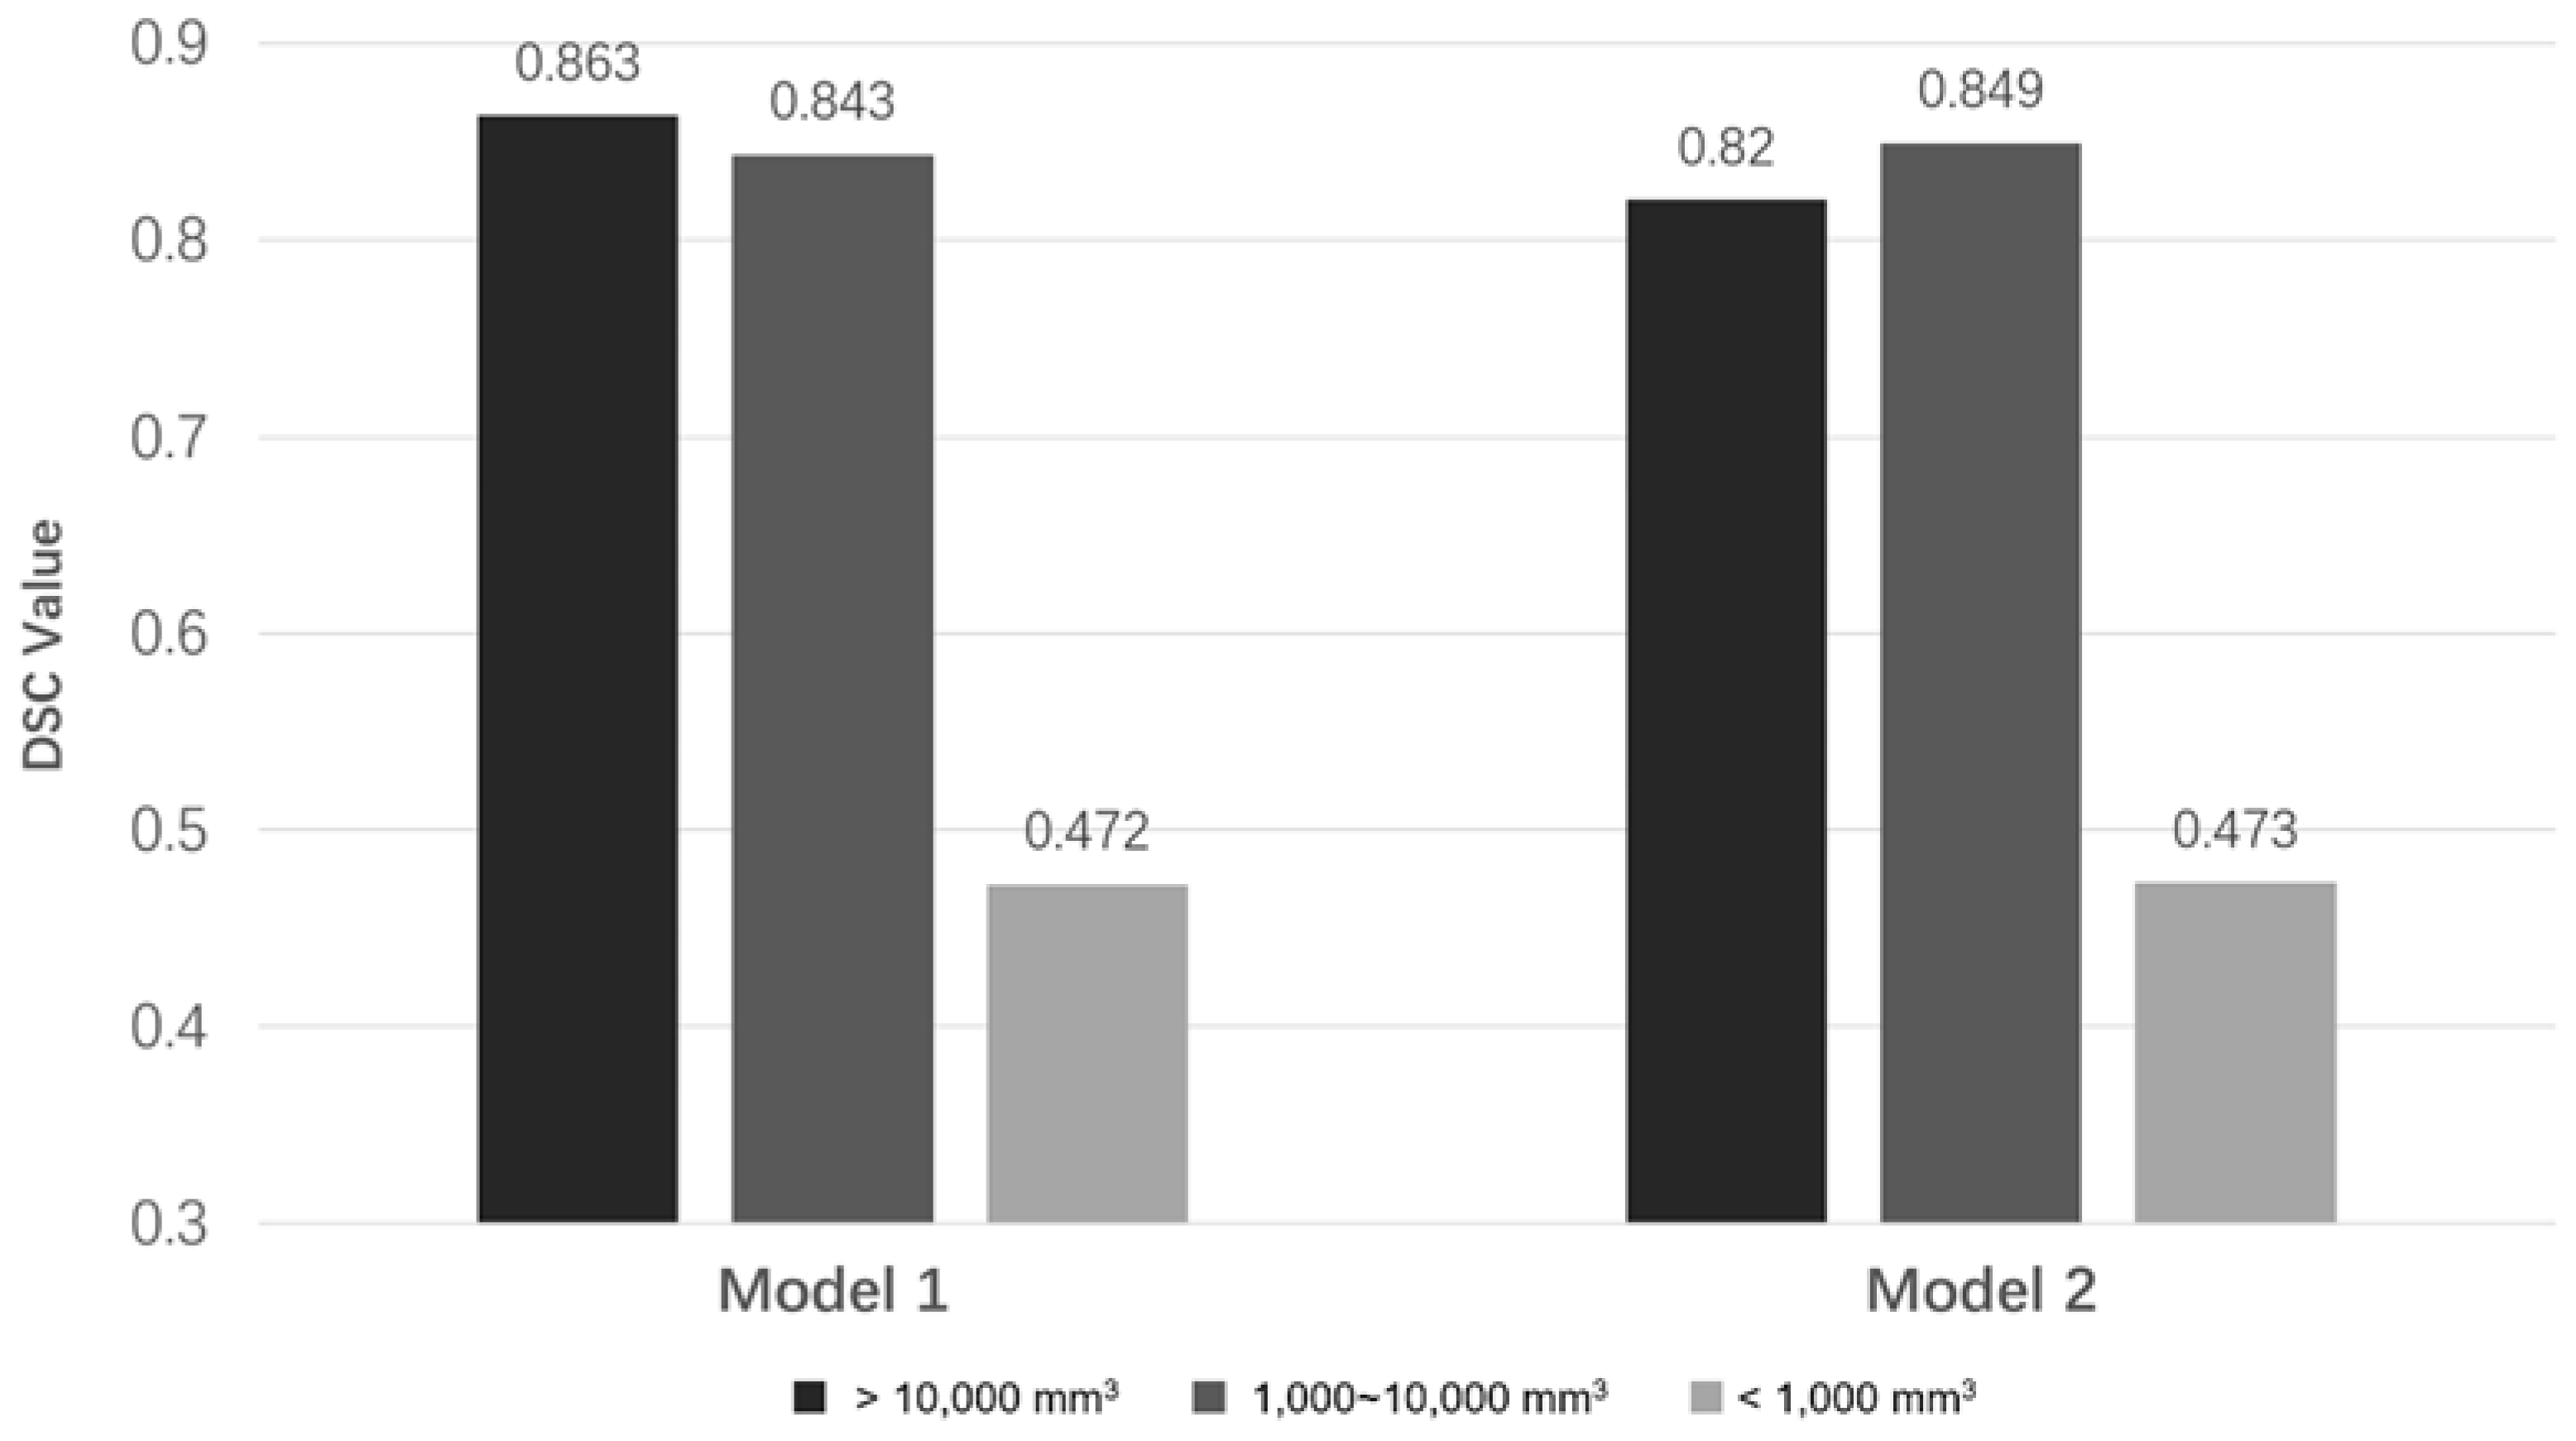

3.6. The Relationship between DSC Values and PA Volumes

| Large (≥10,000 mm3) | 3 | 0.863 | 0.820 |

| Medium (1000~10,000 mm3) | 21 | 0.843 | 0.849 |

| Small (≤1000 mm3) | 11 | 0.472 | 0.473 |